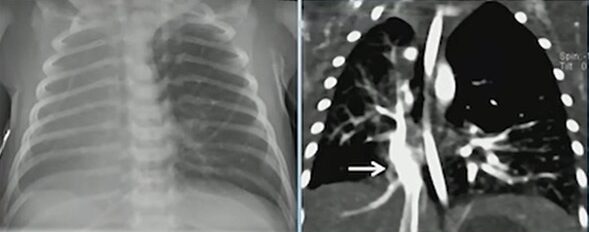

Scimitar syndrome (RLL PAPVR) with R Lung hypoplasia

The hallmark is a right lower lobe pulmonary vein draining anomalously—most often into the inferior vena cava, but occasionally into the inferior right atrium. This vein produces the classic “scimitar” appearance on chest radiography and cross-sectional imaging. Children often have concurrent right lung hypoplasia, which alters airway and vascular proportions.

Scimitar Syndrome (“Scimitar Vein”)